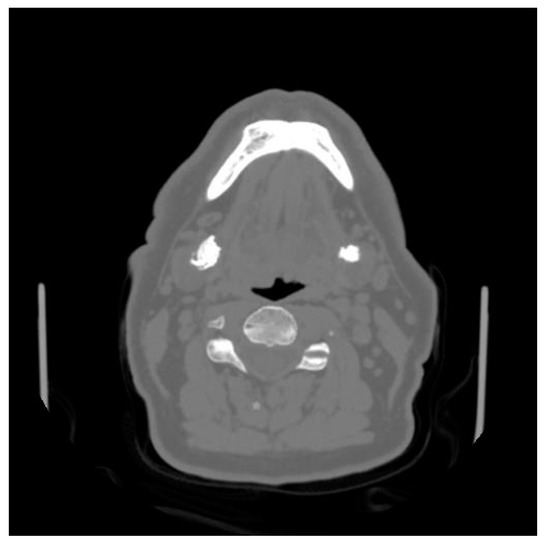

The patient underwent pre-operative CT showing two hilo-parenchymal submandibular gland stones, 20 mm on the right submandibular gland and 10 mm on the left gland (Figure 1).

Figure 1.

Axial CT scan showing the two stones.